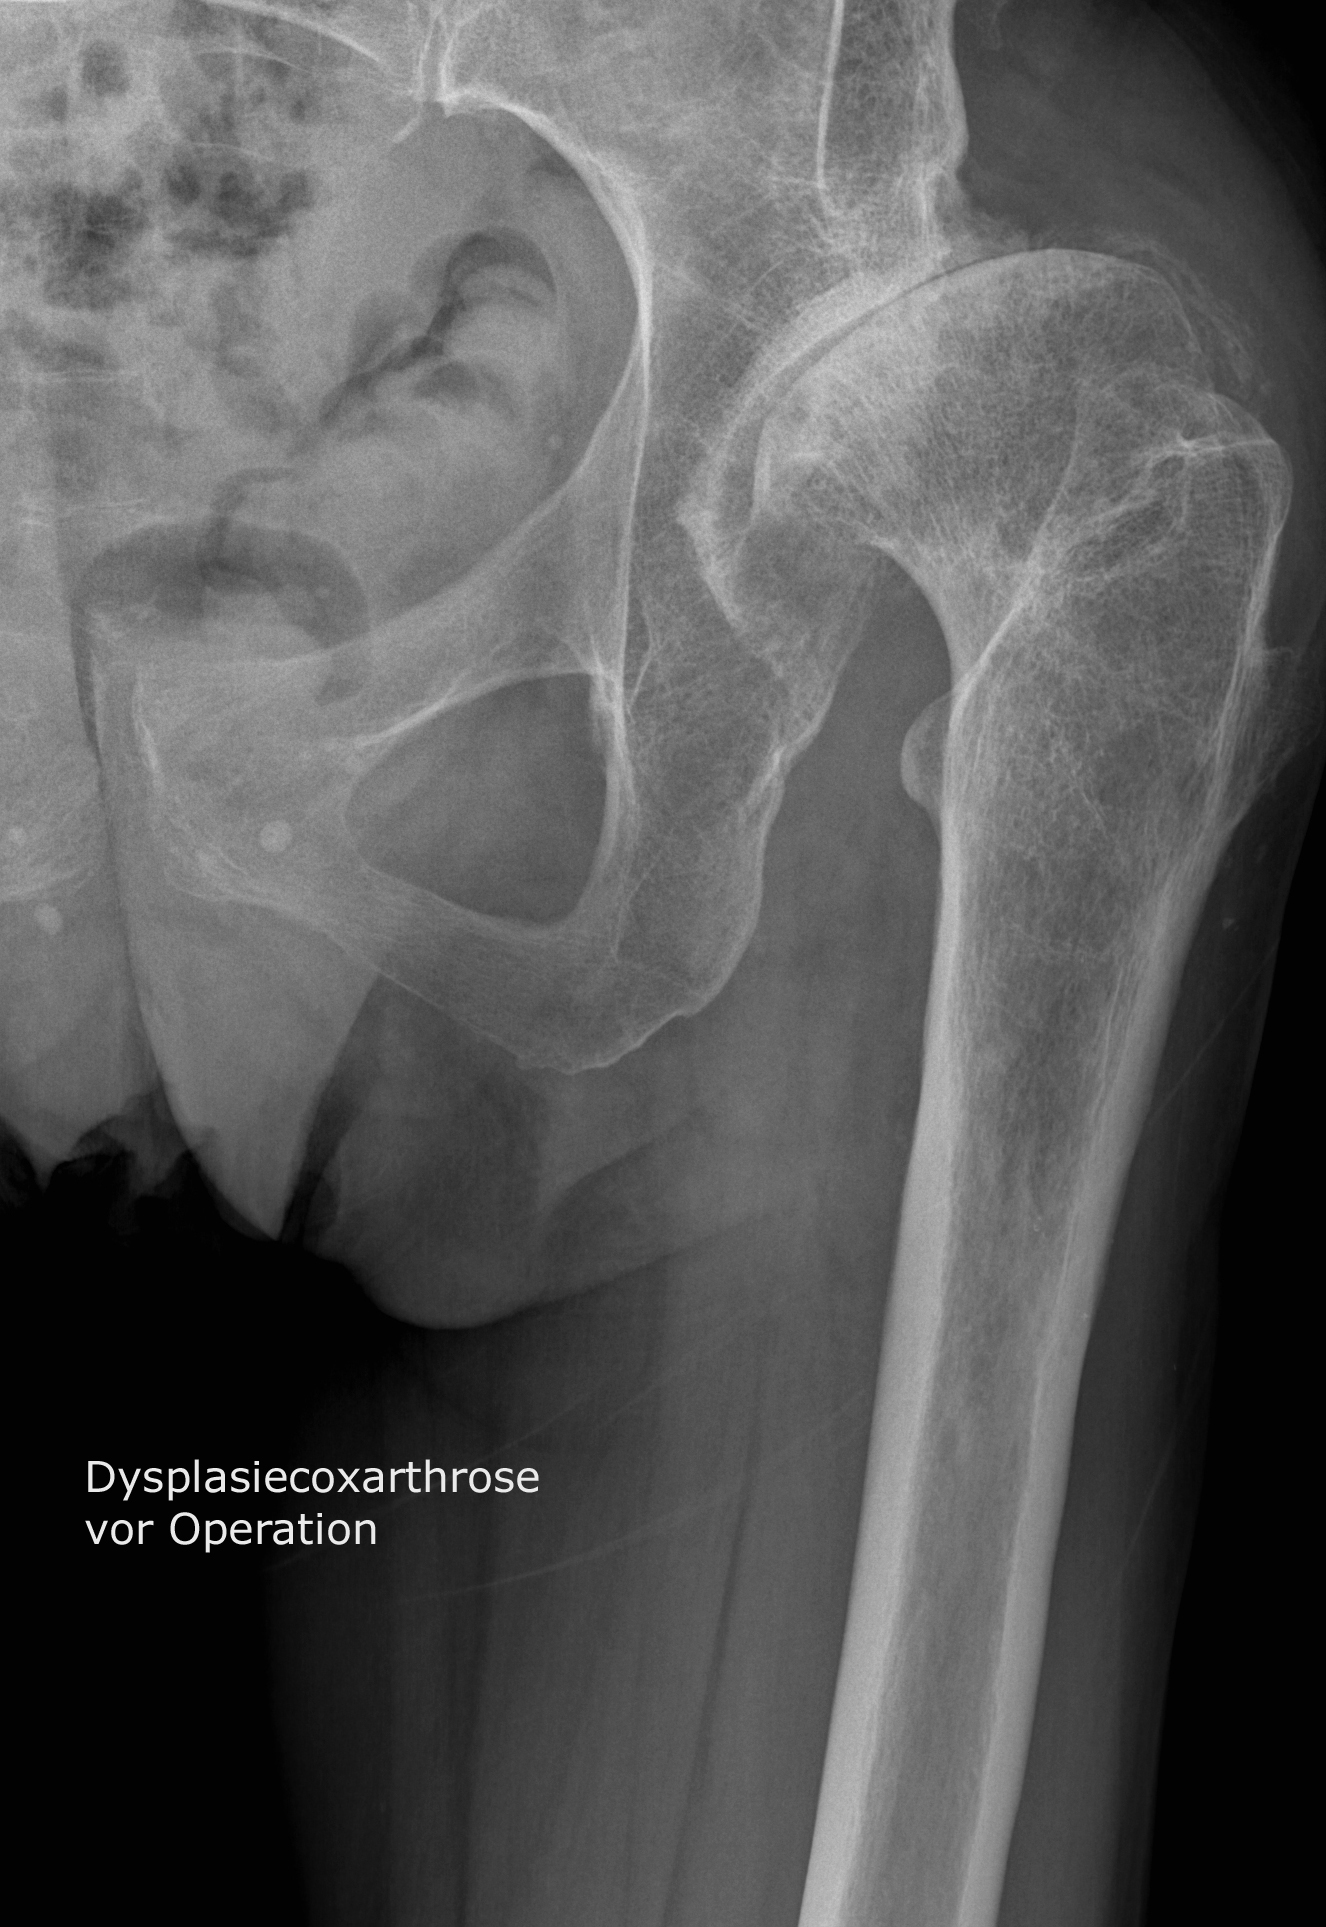

Coxarthrose (deutsch: Koxarthrose oder Hüftarthrose) ist eine degenerative, nicht-entzündliche Gelenkerkrankung der Hüfte: Die Knorpelschicht zwischen Hüftkopf und Hüftpfanne nutzt sich langsam fortschreitend ab. Wenn der Gelenkknorpel schließlich dünner wird, drohen die knöchernen Gelenkflächen aufeinanderzureiben.. Den Verschleiß des Hüftgelenkes bezeichnet der Mediziner als Coxarthrose. Diese kann sowohl unter Belastung, aber auch im Ruhezustand zu starken Schmerzen führen. Ferner kann die Beweglichkeit des Gelenks deutlich eingeschränkt sein. Woran erkennt man eine mögliche Hüftgelenksarthrose? Wann ist eine Operation sinnvoll?